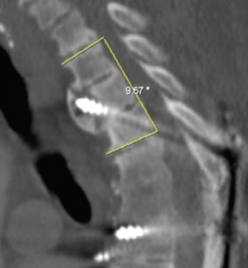

图18 固定近端交界性后凸角>5°

A:术前固定近端交界性后凸角>5°;B:上固定椎未跨过此区域;C:术后随访出现PJK